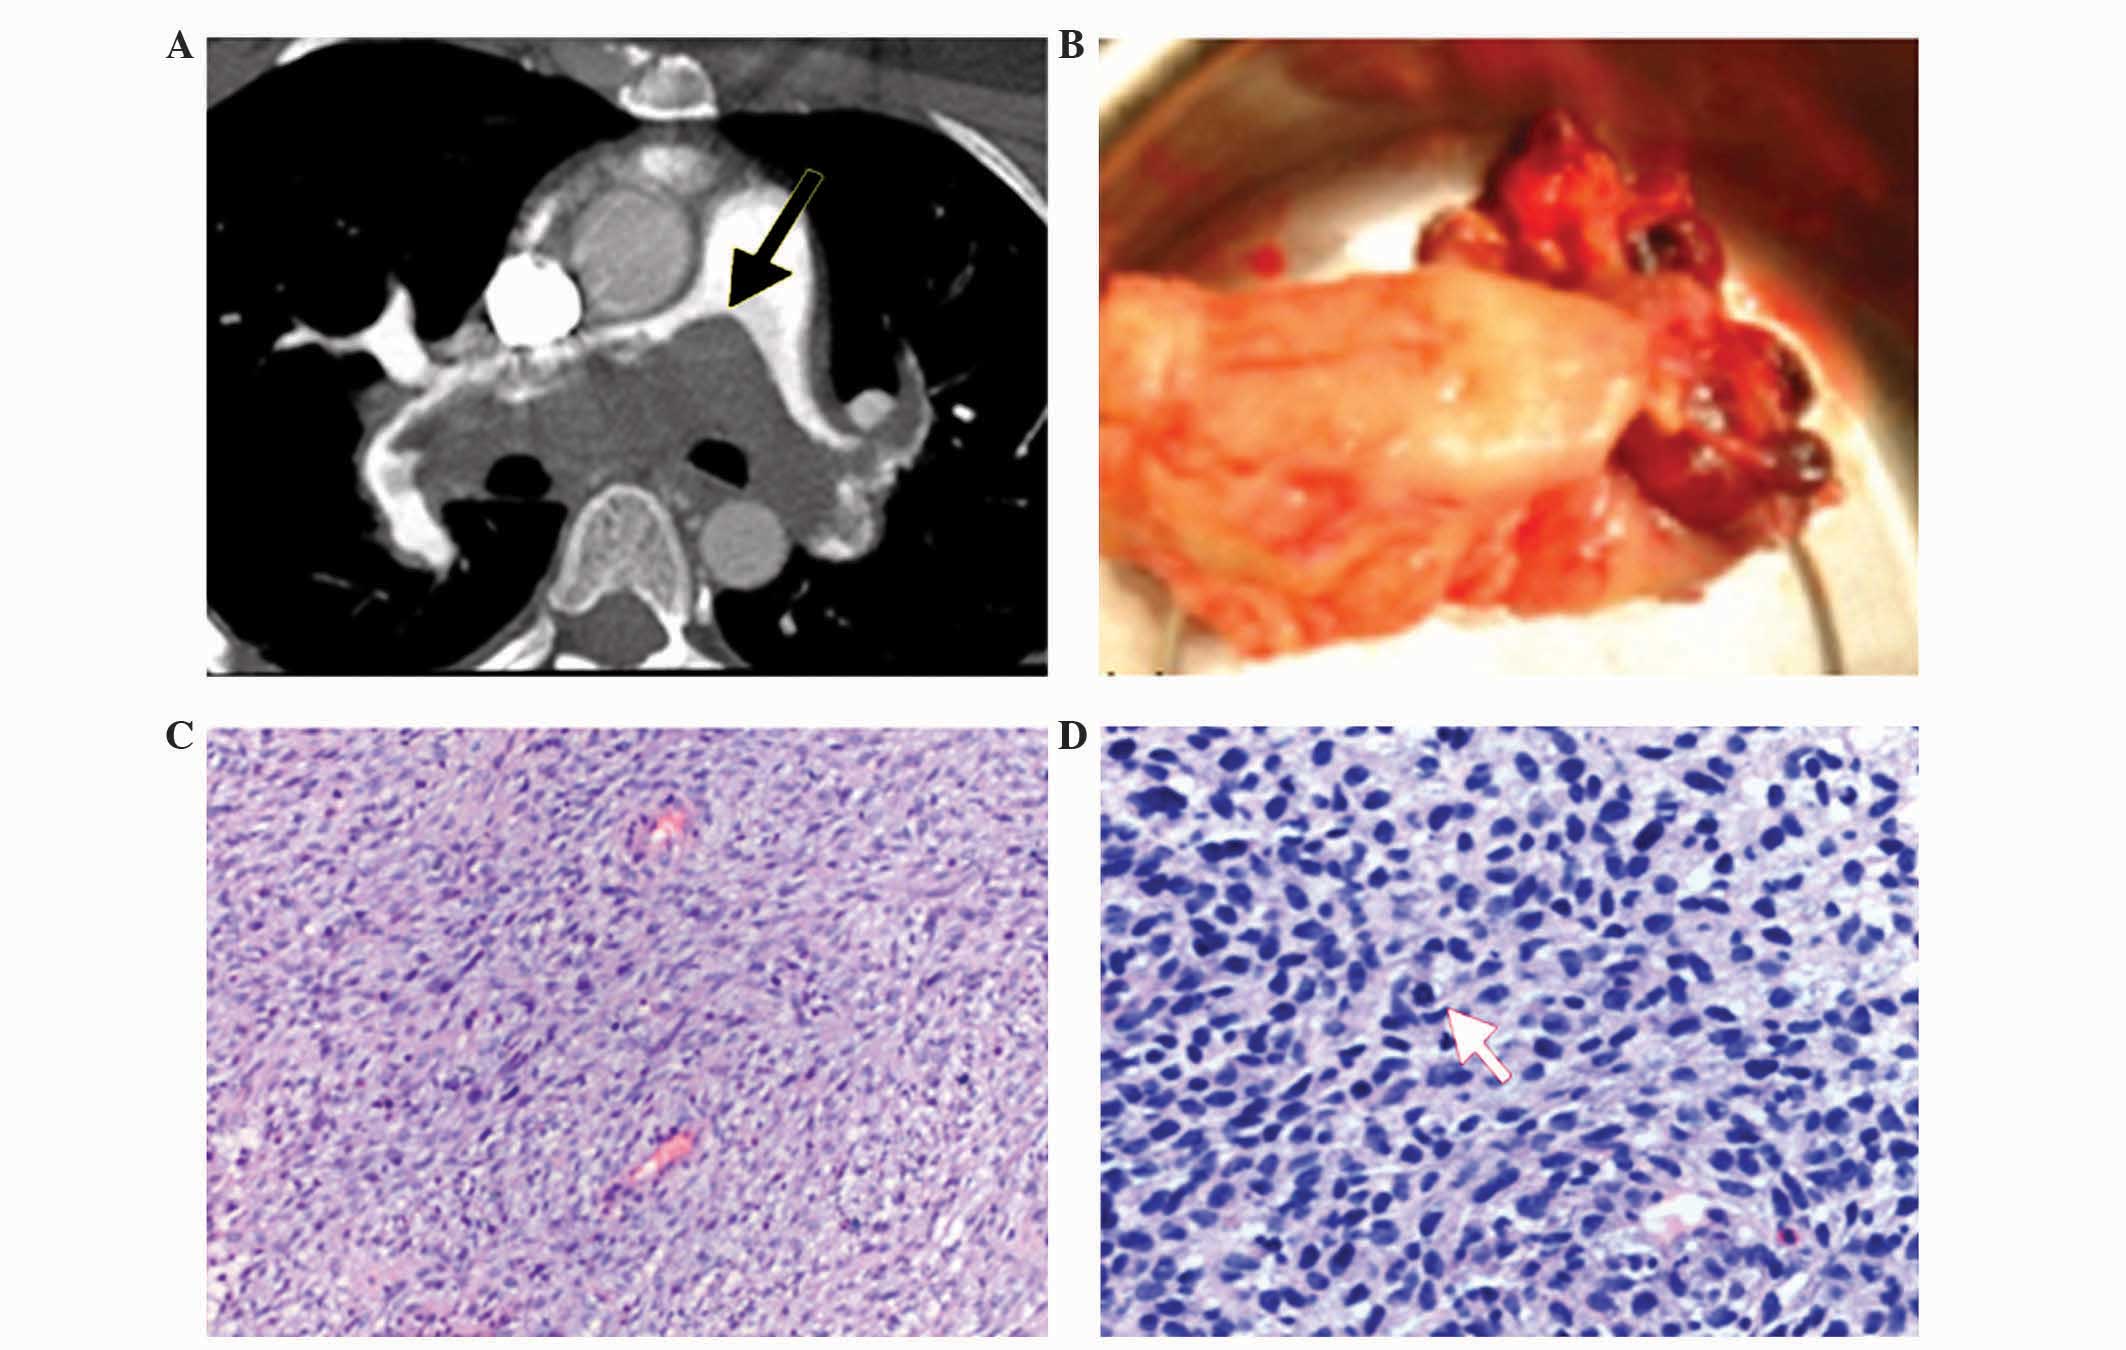

Pulmonary artery sarcoma (PAS) is an extremely rare and highly malignant tumor that originates in the pulmonary artery. The majority of reported cases of PAS are confirmed by pathological examination subsequent to surgery or by autopsy. The present study reports the clinicopathological characteristics and immunohistochemical phenotypes of three cases of PAS, and aims to facilitate the identification of this lethal disease. In the present study, the data from clinical, histopathological and immunohistochemical examinations of three patients with PAS, whose diagnoses were confirmed by surgical biopsy conducted at the Beijing Anzhen Hospital (Beijing, China) between 2008 and 2012, were retrospectively analyzed. The patients (two women and one man; average age, 41.3 years old) presented with dyspnea on exertion. In addition, two of the patients experienced chest tightness, and one patient experienced intermittent syncope. Computed tomography pulmonary angiography revealed that two of the patients possessed a filling defect in the main, left and right pulmonary arteries, and one patient possessed a filling defect in the right upper pulmonary artery. Macroscopically, the PAS appeared as a mucoid intraluminal or nodular sessile mass spreading along the pulmonary artery. Microscopically, the tumor consisted of spindle cells with fascicular and storiform patterns, and was accompanied by necrosis and stromal myxoid changes. Immunohistochemically, vimentin, desmin and cluster of differentiation 34 were highly expressed in the patient that was diagnosed with intimal sarcoma, while vimentin and α‑smooth muscle actin were highly expressed in the other two patients, who were diagnosed with leiomyosarcoma. PAS is often misdiagnosed due to nonspecific clinical manifestations and radiological features. Therefore, the diagnosis of PAS should be based on typical morphological features and immunohistochemical analysis of the tumor tissue.